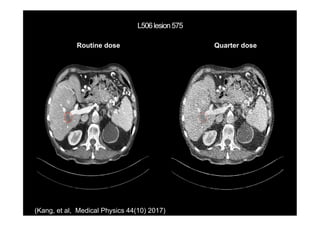

(Kang, et al, Medical Physics 44(10))

Routine dose Quarter dose

(Kang, et al, Medical Physics 44(10) 2017)